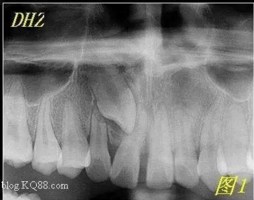

最近朋友圈轉(zhuǎn)發(fā)最多的一張片子,你知道嗎?

1.png